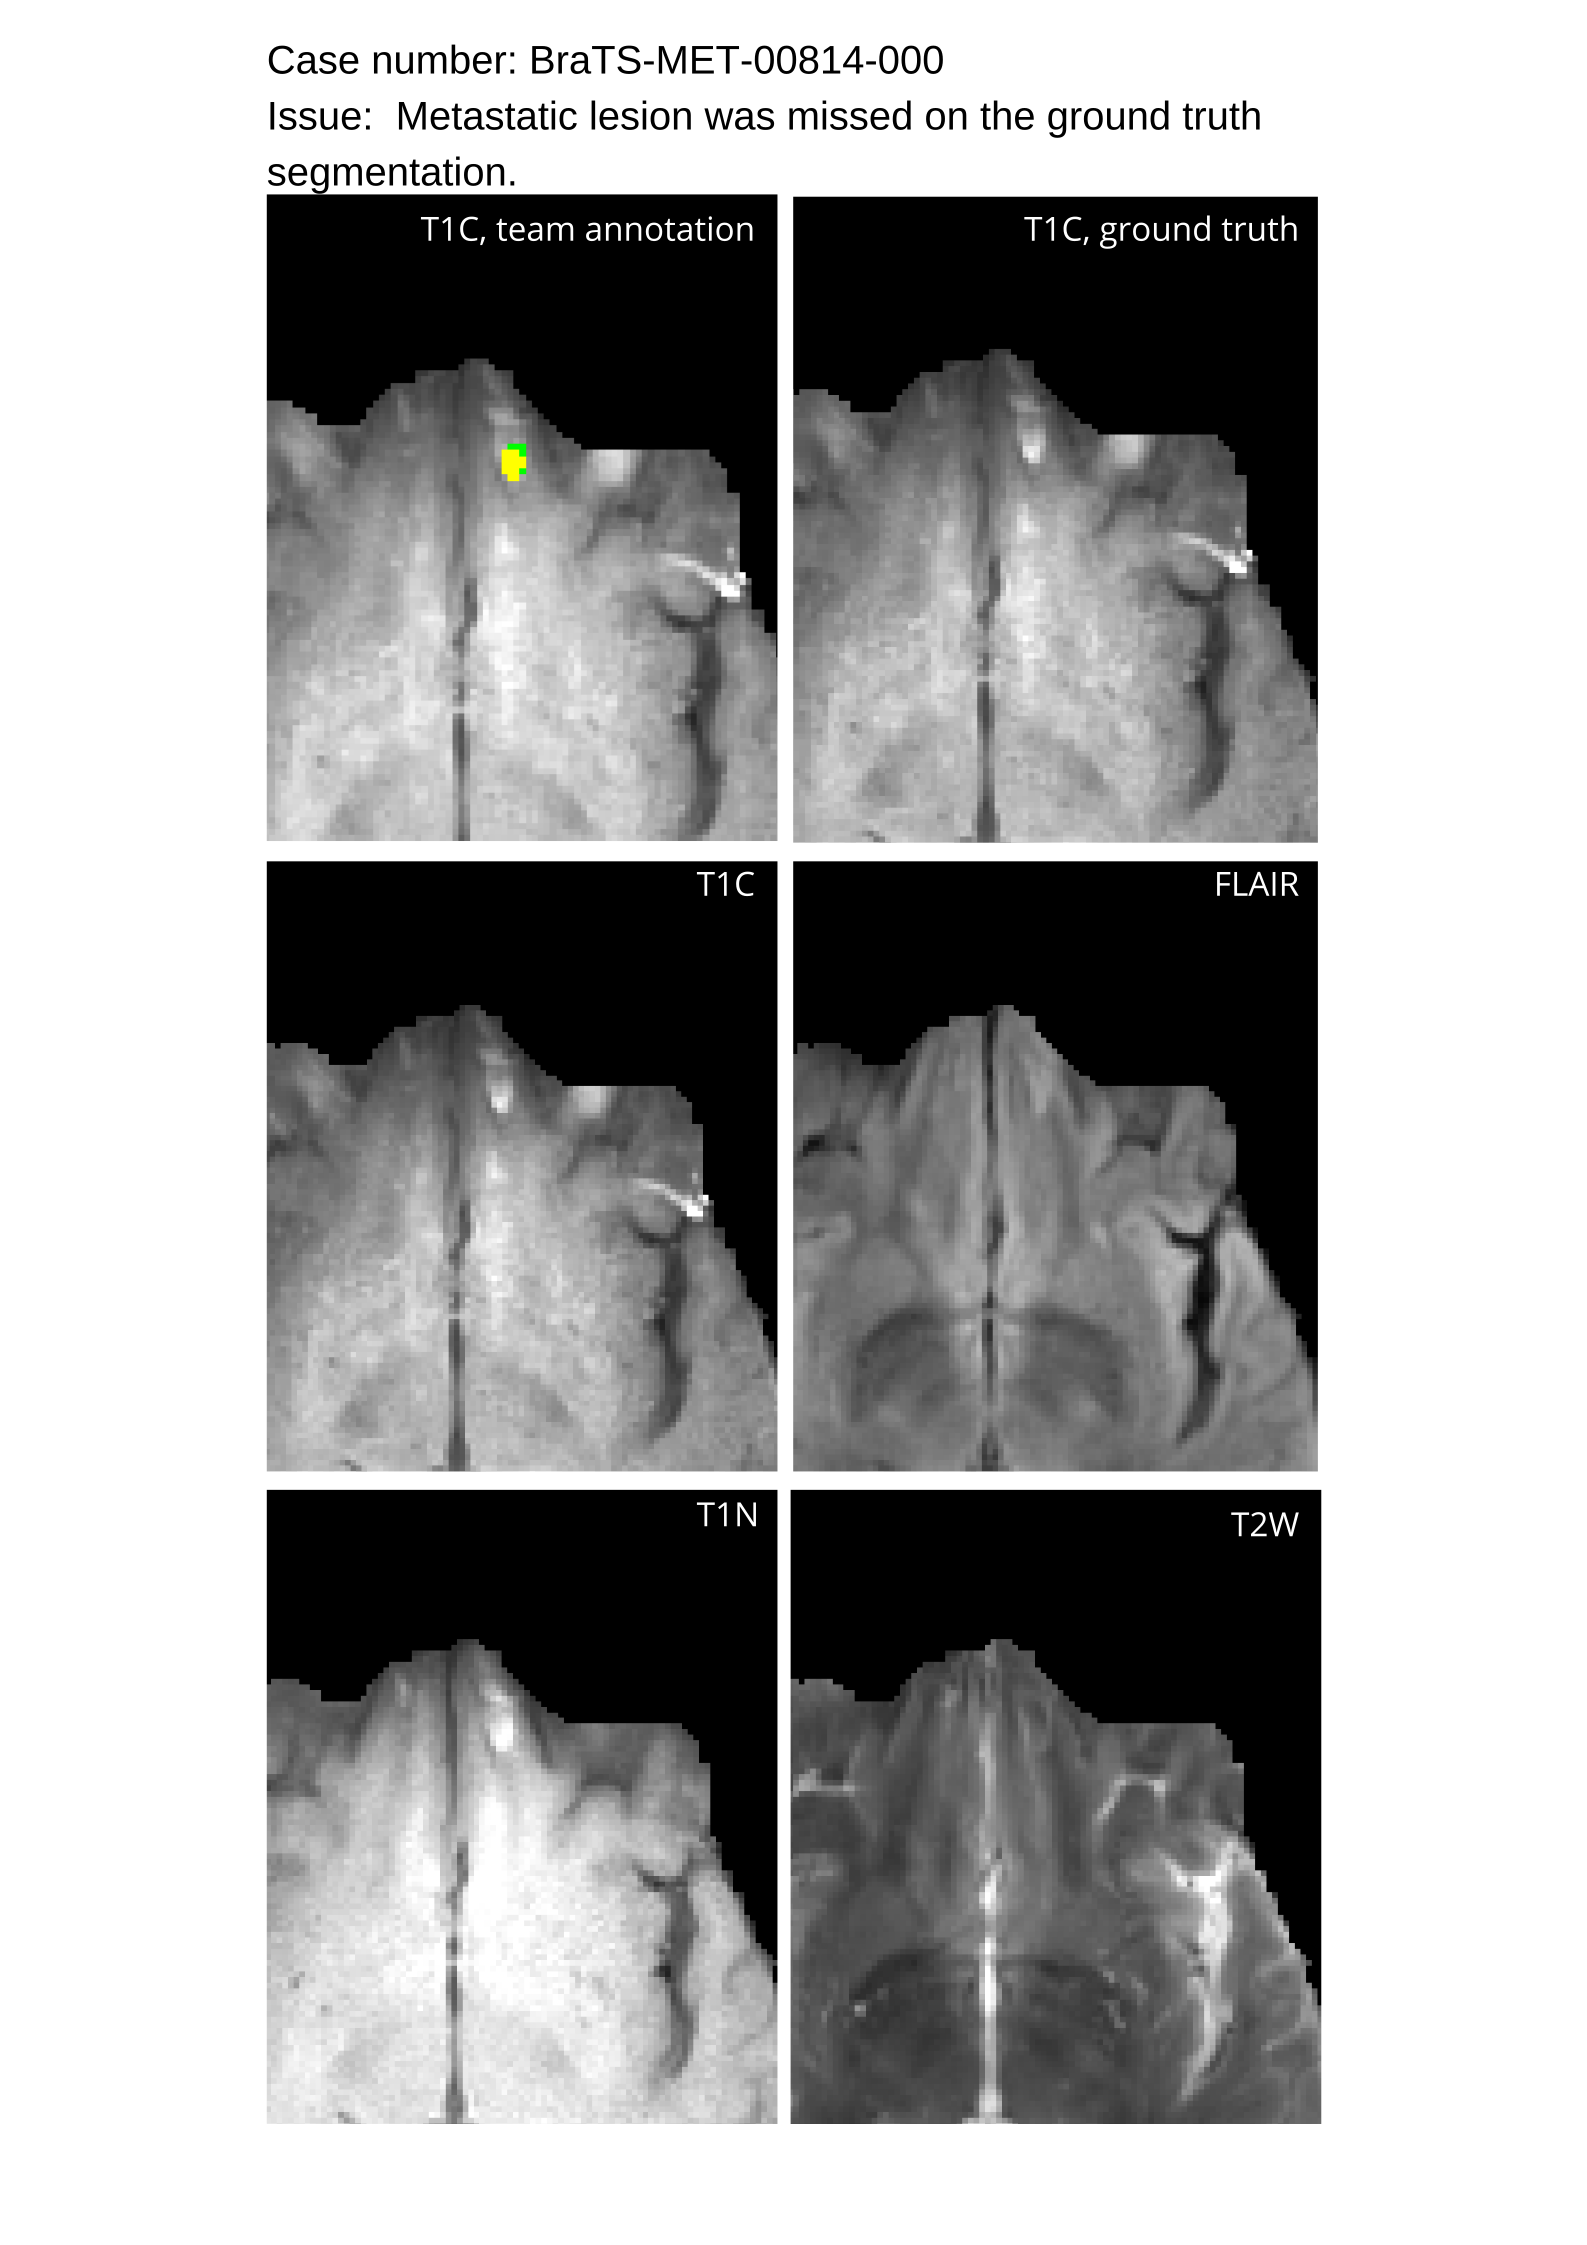

Approvers reviewed the volunteer annotations and either approved the case or returned it to students for re-annotation. Additionally, a QC process was implemented, which included removing all random voxels and any voxels outside the brain mask, ensuring all images had the same parameters (space, orientation, and origin) as the SRI24 atlas, and verifying the presence of all segmentations and segmentation masks are in the folder with original NIfTI images.

Automated algorithms missing small metastases. Enhancing metastasis was fused using the minority voting algorithm to aggregate all enhancing tumor voxels identified by the three algorithms. However, many small metastases were missed and were manually segmented by neuroradiology attendings.

Acknowledging the variability in lesion significance arising due to human error, a volumetric threshold of 2 voxels (2 mm3superscriptmm3\text{mm}^{3}mm start_POSTSUPERSCRIPT 3 end_POSTSUPERSCRIPT) was established by an expert panel of clinical radiologists, below which the models’ performance on deemed ”small/false” lesions is not considered in the evaluation. This approach was primarily adopted to ensure that participants were not unfairly penalized for stray voxels in the GT labels, which may result from human error, or for small lesions unrelated to the pathology central to the challenge. The expert panel of clinical radiologists also determined the dilation factor, which was uniformly applied for combining lesions in the GT masks. A dilation factor of 1 voxel in 3D space was chosen because BMs can be small, and it is important to avoid combining these small BMs.

Table 4 provides the relative ranking for each team. Team NVAUTO ranked first in the challenge, with an average rank across subjects of 7.9 and a PatientWise mean of 0.38. Team SY placed second with a PatientWise mean of 0.41 across all patients. The supplementary material depicts the pitfall cases with figures illustrating the false positives or missed lesions.